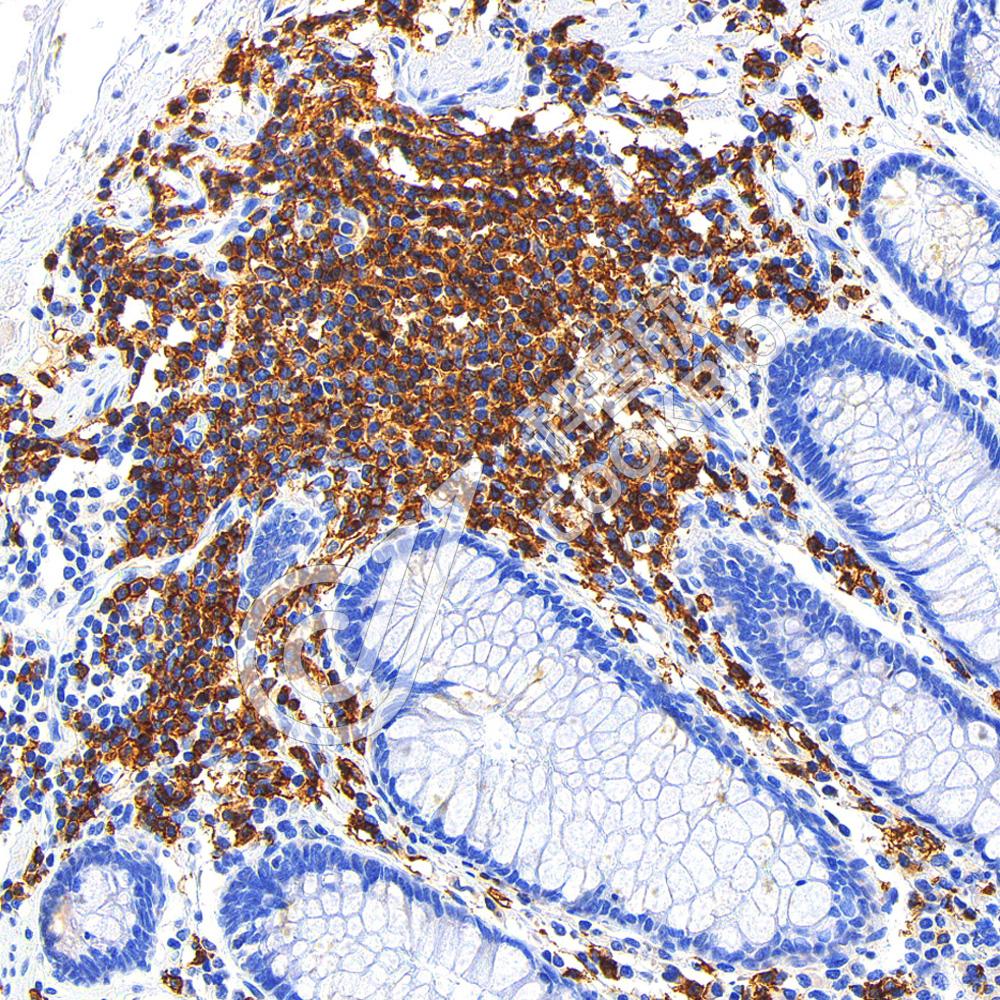

IHC检测CD20蛋白(货号 K1347163).

样品: 人结肠癌, 4%多聚甲醛 (货号KSG1101) 固定12-24小时.

抗原修复: Tris-EDTA抗原修复液(pH 9.0) (KSG1203), 98℃, 20分钟.

—抗: 1: 600稀释, 4℃ 孵育过夜.

二抗: S-vision免疫组化多聚二抗(山羊抗兔),即用型 (货号KB3906), 室温孵育20分钟.